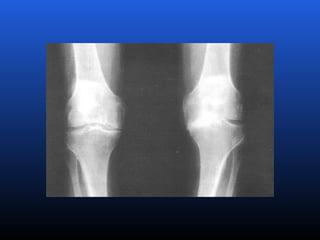

RADIOLOGIA

No início da doença não se observam anormalidades.

Com seu desenvolvimento, observam-se:

 Diminuição do espaço intra-articular

 Esclerose subcondral (eburnação)

 Osteófitos;

 Erosão e anquilose óssea (pseudocistos ósseos).